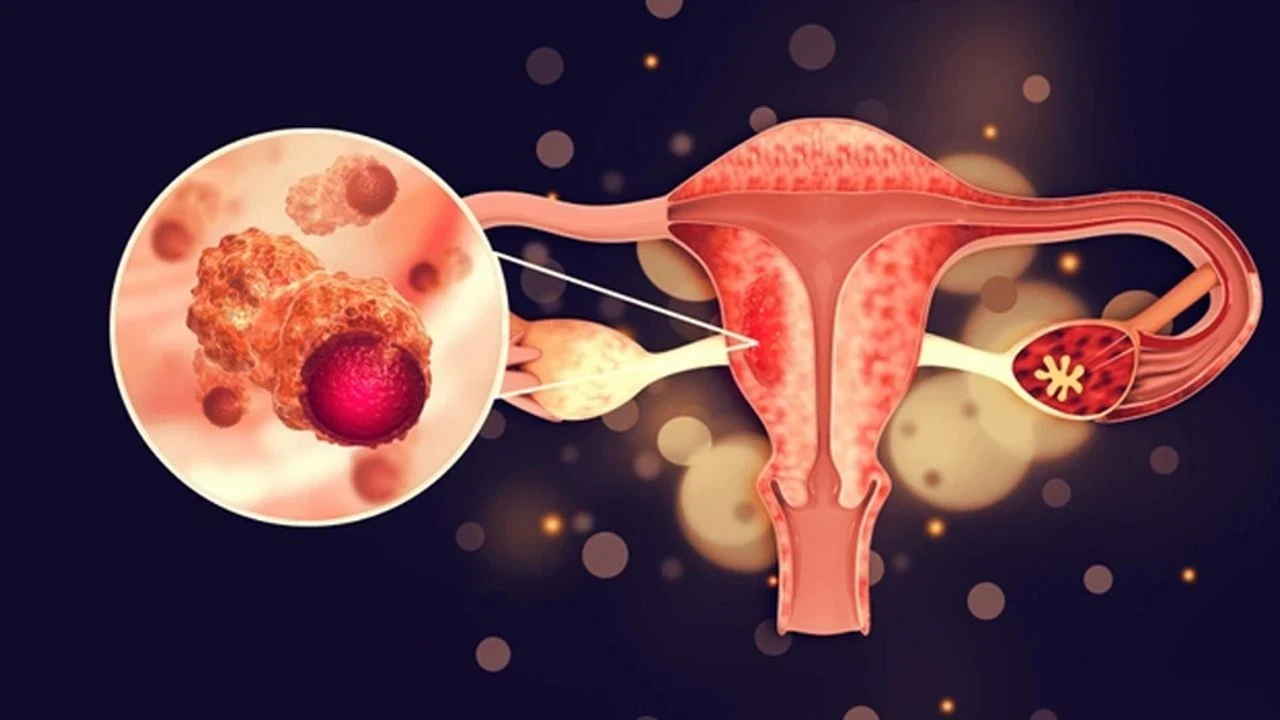

Yumurtalık Zayıflığı Hamile Kalmayı Engeller Mi?

Yumurtalık zayıflığı olan kadınlar, genellikle doğal yollarla hamile kalmakta zorlanır. Ancak bu durum, hamile kalmanın tamamen imkânsız olduğu anlamına gelmez. Modern tıpta birçok yöntem, bu kadınlara anne olma şansı sunar:

- Tüp Bebek Tedavisi: Yumurtalık rezervi düşük olan kadınlar için etkili bir yöntemdir.

- Yumurtalık Stimülasyonu: Hormonal ilaçlarla yumurtalıkların daha fazla yumurta üretmesi sağlanabilir.

- Donör Yumurtası: Kendi yumurtalıkları yetersiz olan kadınlar, donör yumurtasıyla hamile kalabilir.

- Doğal Yöntemler: Nadiren de olsa bazı kadınlar, düzenli yaşam tarzı değişiklikleriyle doğal yollarla hamile kalabilir.

Yumurtalık zayıflığı tamamen tedavi edilemez, ancak semptomlar yönetilebilir ve yardımcı üreme teknikleri ile hamilelik şansı artırılabilir.

Yumurtalık zayıflığı olan biri doğal yollarla hamile kalabilir mi?

Nadir durumlarda mümkün olmakla birlikte, yardımcı üreme teknikleri genellikle daha etkili bir yöntemdir.

Yumurtalık zayıflığı, kadın sağlığı açısından önemli bir sorun olsa da tıpta kaydedilen ilerlemeler sayesinde bu durumdaki kadınlar için birçok çözüm yolu bulunmaktadır. Erken tanı ve uygun tedavi yöntemleri ile anne olma hayaline bir adım daha yaklaşmak mümkün. Sorununuzu bir uzmanla paylaşmaktan çekinmeyin ve doğru bilgiyle harekete geçin.